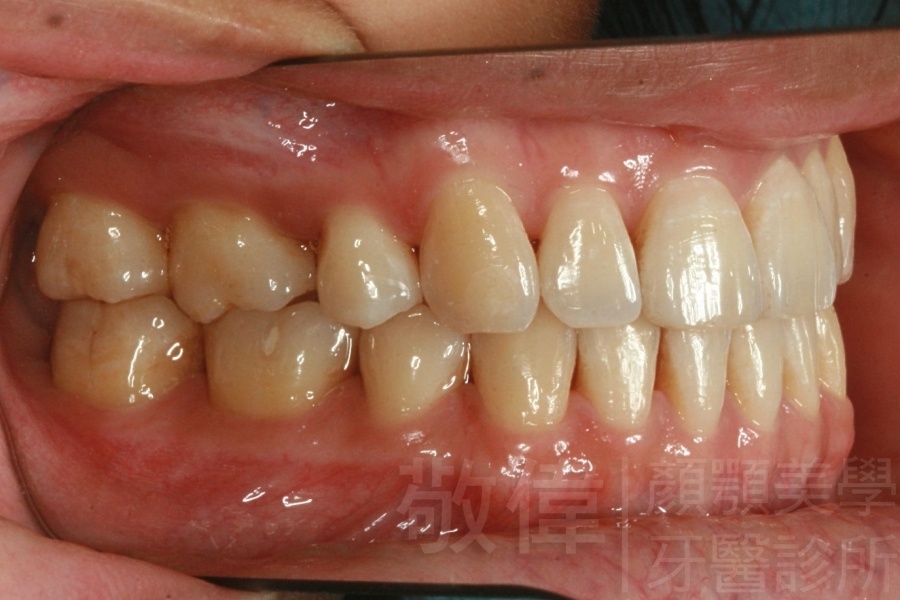

變臉矯正,原來戽斗妹跟大歪臉變成自信正妹

經由本院3D數影X光影像儀分析、與3D齒顎顏矯正技術,再配合口腔顎面正顎專科醫師施以正顎手術治療,雙方共同合作,使患者臉部外觀有很好的改善,大歪變小歪,產生了天南地北的大改變,她的人生也整個變得不一樣。

因為矯正與正顎手術的配合,使「戽斗妹」變成了「陽光正妹」,完全的改變了她的人生,在面對各種場合、與人交際都散發出自信微笑。所以,奉勸家長,如果小朋友有臉顎畸型的問題,應該考慮配合做這種簡單、安全、有效的正顎手術。